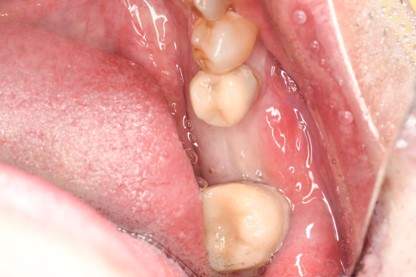

口腔内写真

- Befor

- After

| 年齢 | 50代・男性 |

| 主訴 | 左上7番 左下5番7番 |

| 治療内容 | ・インプラント埋入 ※1:GBR(骨造成)・・・骨再生誘導法。骨の高さや厚みを人工骨や人工膜などを使用し再生する方法 |

| 治療費 | 合計:1,809,500円(税込) ■内訳 ・左上7番 ・左下5番7番 |

| 治療期間 | 左上7番約1年 左下5番7番約10ヵ月 |

| 治療方針 | 左上7番は昔他院で被せものをしており、被せものの中が歯ぐきの中まで虫歯になっていたため抜歯せざるを得ない状態だった。抜歯と同時に骨造成を行い、骨が出来るまで4ヵ月待ってからインプラントを埋入した。 ※2ポンティック・・・歯のない部分を補うダミーの歯。 |

| 担当者所見 | 元々金属の被せものが多く入っていたため、2次カリエス※3が多かった。今回は金属ではなく、ジルコニアを使用し、2次カリエスにならないよう、患者様にはブラッシング指導とメンテナンスの重要性をお伝えした。 ※3二次カリエス・・・詰め物や被せものを入れた歯が虫歯になること。 |